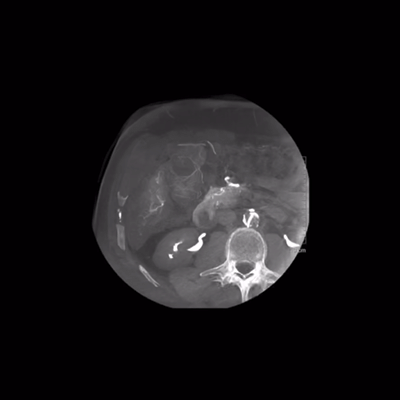

其选择性程序中的清晰可视化,西门子称基于对比度的曝光控制,OPTIQ可达到的最低剂量,以提供最佳对比度为2D成像中的小血管和设备提供出色的可见性。

图片来源于:西门子官网